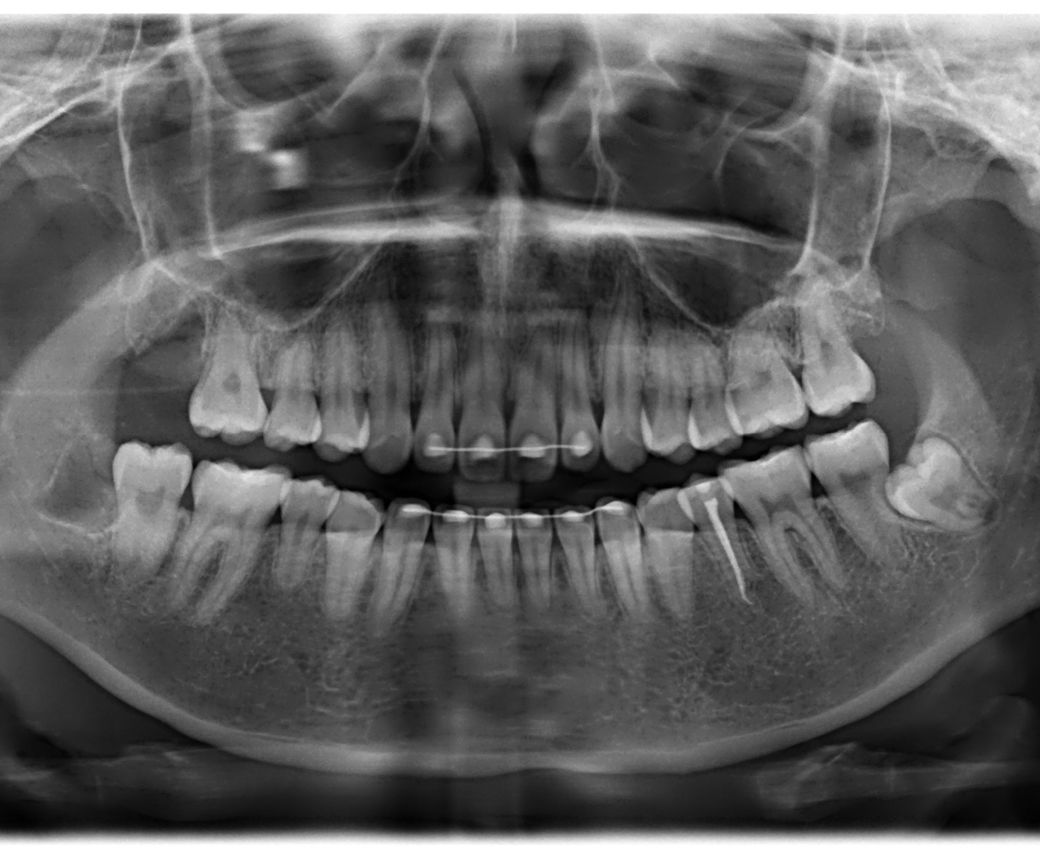

사진상 왼쪽 위에 어금니가 선천적으로 없습니다. 교정치과에선 사랑니가 잘 나오면 대체해서 쓰라고 하셨습니다. 이번에 사랑니 발치 치과를 가니 염증 유발성이 있어 발치하는게 좋겠다고 뽑으셨고 어금니 임플란트 추천을 해주셨습니다. 제가 엑스레이 보기엔 사랑니가 잘 내려오고 있는 편인거 같은데 의사 전문가 입장에선 어금니 대체가 불가능한 치아 상태였나요? 이미 뽑아버렸지만 제 치아를 사용할 수 있는 기회였는데 아깝기도 하고 궁금해서 여쭤봅니다 (사진 순서는 뽑기 전, 후 입니다) 그리고 꼭 임플란트를 해야 할까요? 씹는 것엔 불편함이 없습니다

• 2번 째 사진

2. 저 위치는 반드시 임플란트를 심어야 하는 것은 아닙니다 물론 심으면 저작력에 도움이 되긴 합니다